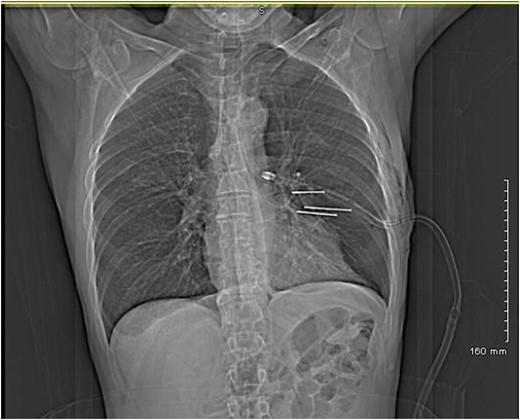

A 64-year-old man referred to our institution with self-inflicted penetrating chest injuries with an electric nail gun. This was in response to express his frustration towards an expensive non-functioning product purchase. Patient used an electric driller to fire in three nails on the chest between left anterior axillary line and left lateral sternal border. Upon arrival to emergency department, on initial assessment according to ATLS protocol, his Glasgow coma score (GCS) was 15, hemodynamically stable with three puncture wounds in his chest medial to his left nipple. He also sustained full thickness electrical burns on the left middle and index fingers and fractured right middle, ring and little fingers. Chest radiograph showed three nails of close proximity to the heart, and a left sided pneumohaemothorax. A chest drain was inserted and a CT thorax was performed (Figs 1 and 2).